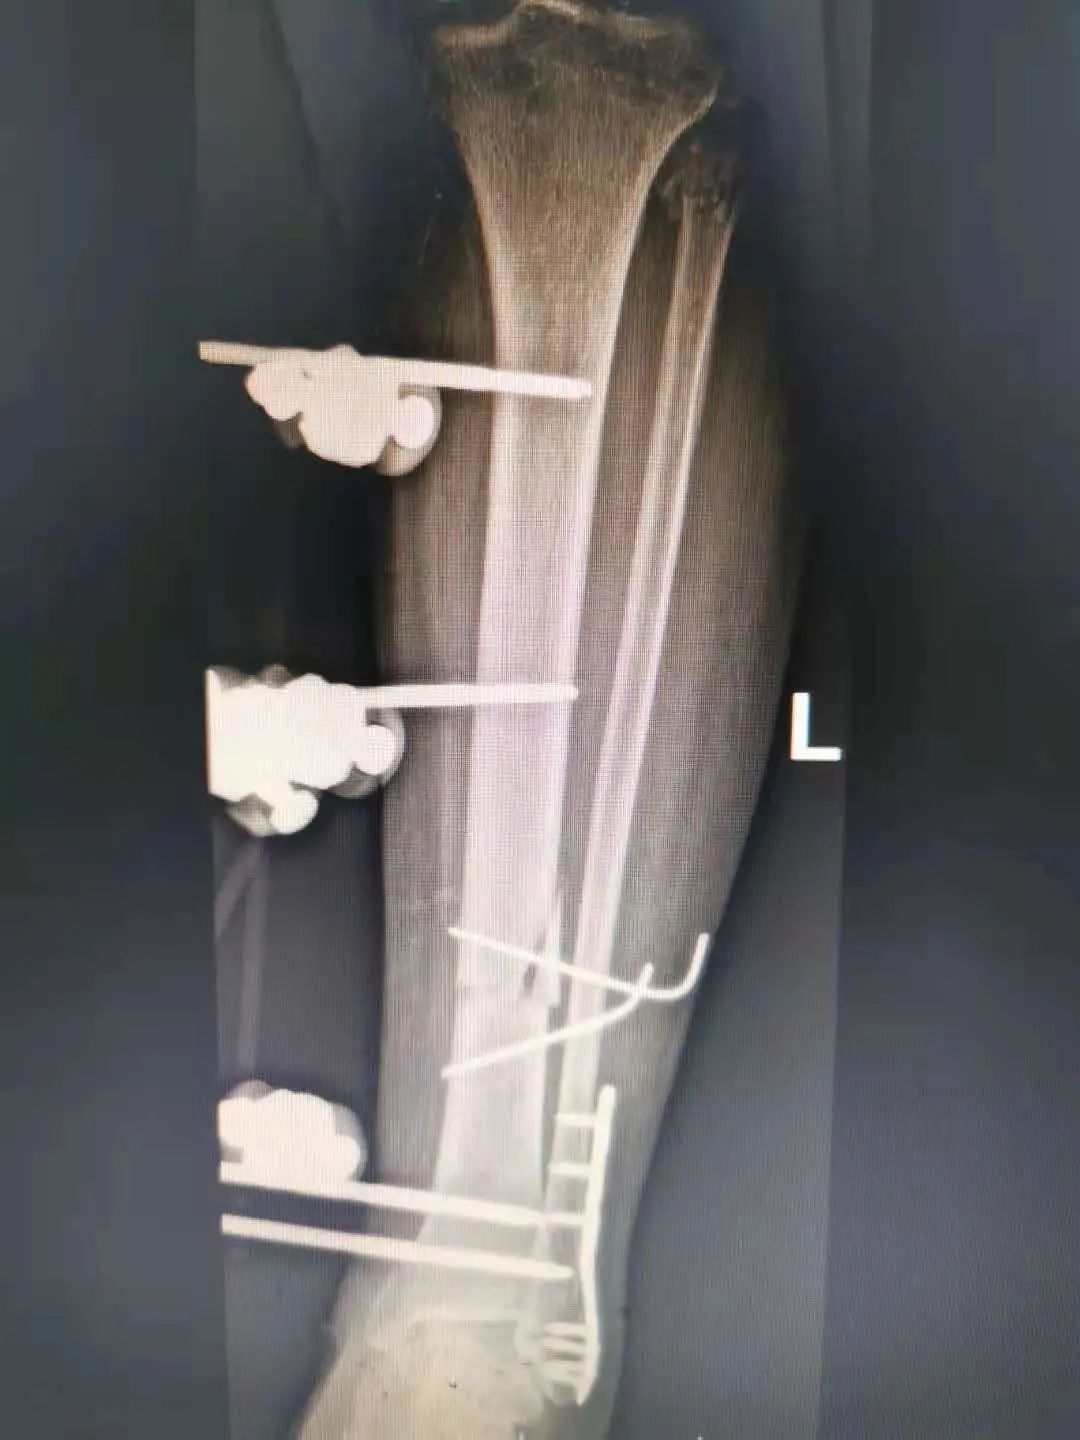

针对吕女士的伤情,骨科一区团队在副主任徐爱贤的带领下进行了周密讨论,对吕女士骨折的治疗方案有两种:一种是内固定,就是将断裂的胫骨复位后用钢板固定;一种是外固定,就是通过一种固定骨骼的器具,在病人骨骼上打入数枚钢针,再安装特制的支架进行固定。选择哪一种方案最

有利于患者呢?胫骨由于其生理特点,骨折好发于中下段,血运差,前内侧软组织覆盖少,如果选择内固定特别是钢板固定,需要剥离骨膜及周围组织,影响断端血运,而且吕女士为开放性骨折,更易发生感染。外固定架可明显避免上述不良影响,更加适合吕女士,且微创,更有利于患者恢

复。

经过与患者及家属的详细沟通,最终确定了外固定的手术方案。经过精心的准备,手术由副主任王学磊主刀,采用“清创+修复软组织+外固定架固定骨折+左侧腓骨骨折切开复位内固定”的方式,用了将近1个半小时,清创彻底、微创固定,手术顺利完成,几天后吕女士顺利拆线出院。